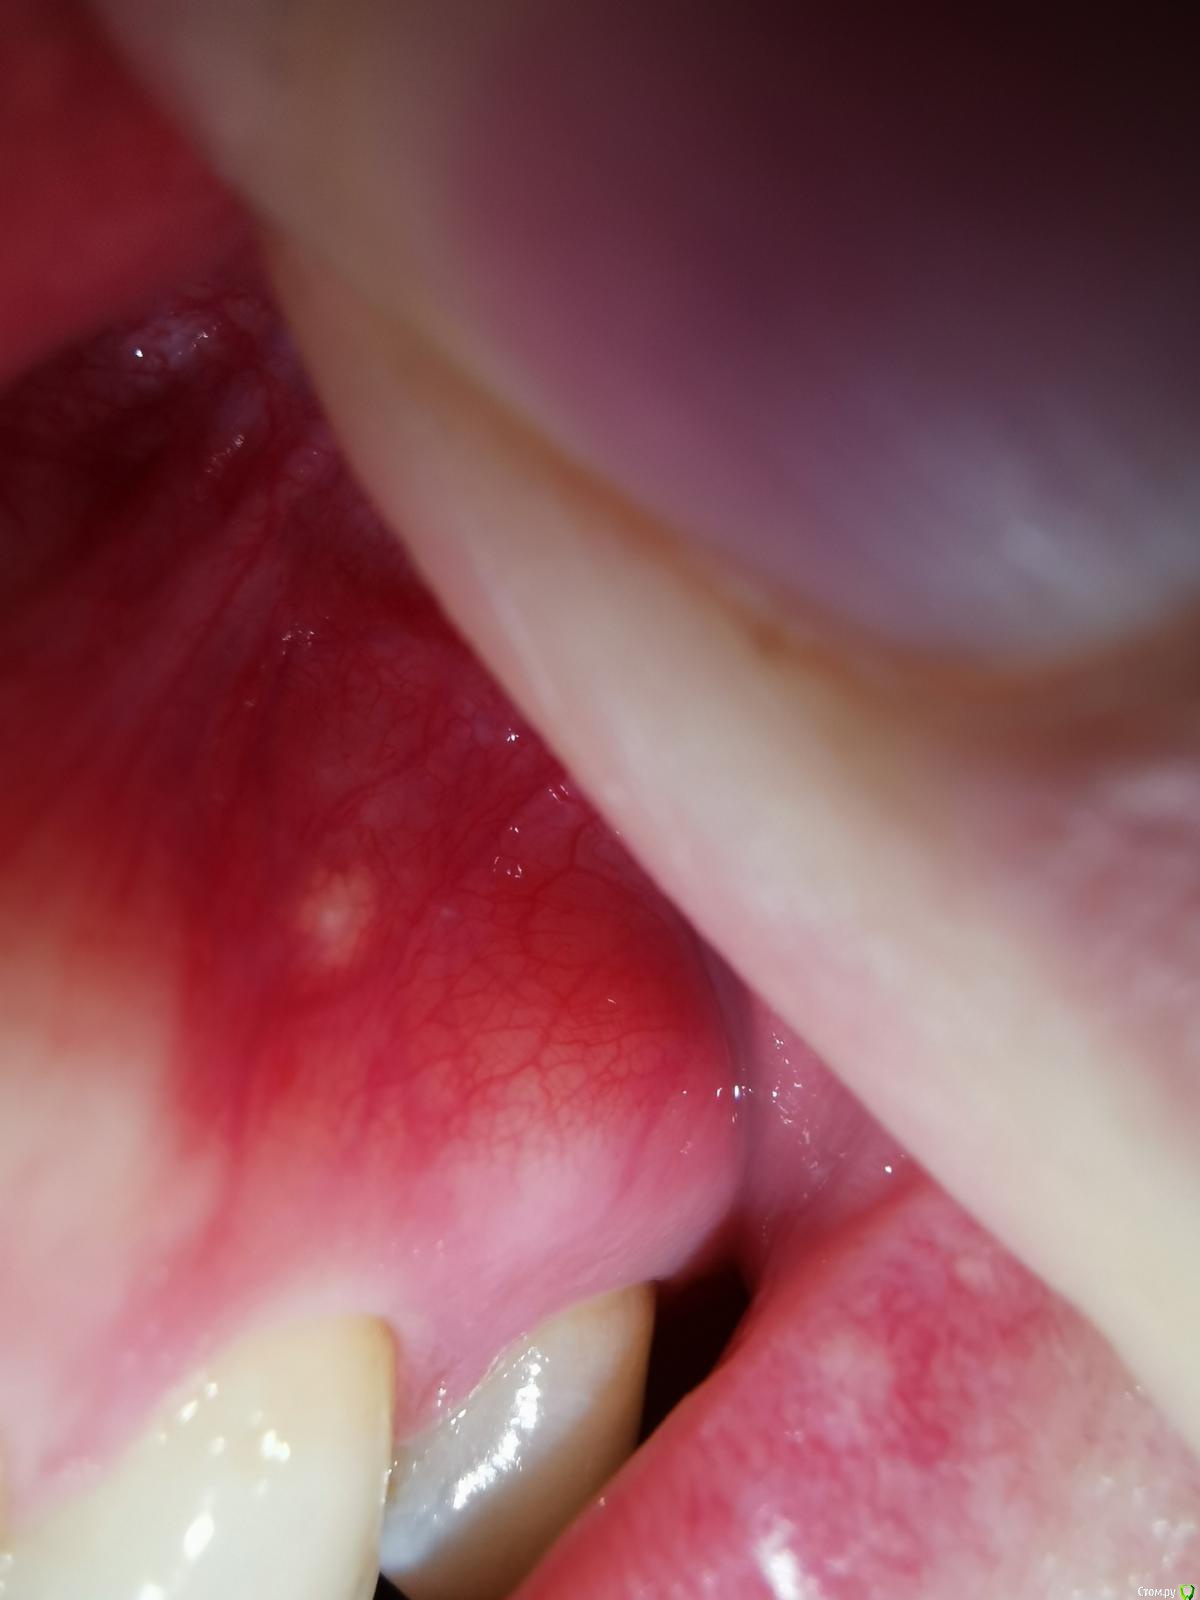

В мае 2020 заметила белое образование на слизистой альвеолярного отростка/десны. Никак не беспокоит, гладкое, не болит, не выпуклое, без изъязвлений, под слизистой не подвижно(не отдельное). Со стороны выглядит как кусочек жировой ткани. С мая месяца увеличилось немного (либо я себе напридумывала...)

Фотографии прикрепляю, не знаю на сколько это будет информативно, но может подскажете чем может являться данное образование?